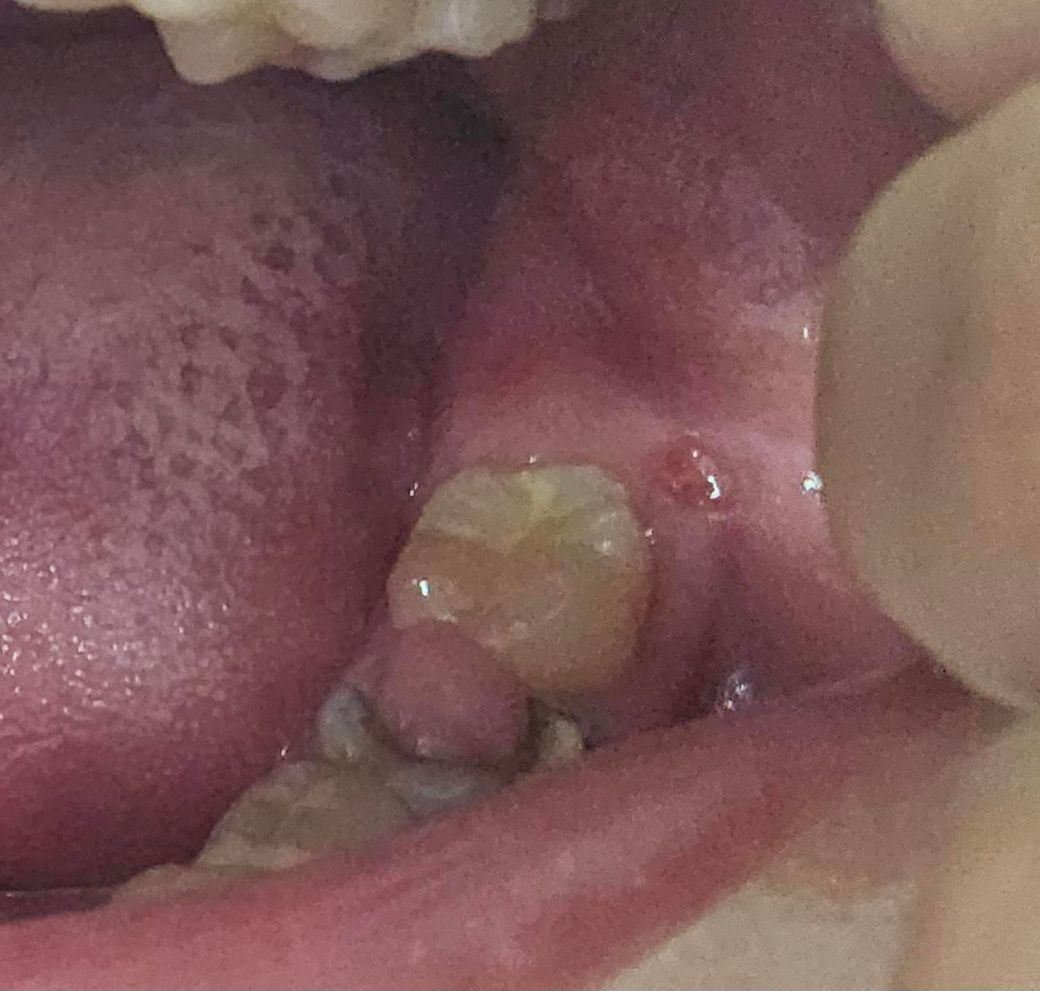

잇뭄 염증 맞을까요 아니면 아니까요?

잇뭄 이거 염증 있가요 따가움 있고 그리고제가가끔씩 염증 생긴는데 이거 따가운데 염증 있가요 알려주세요 그리고 염증 생긴 원인 있나요

• 1번 째 사진

앞쪽 치아의 경우에는 이미 염증이 심하게 진행된 것으로 보입니다. 치과를 바로 가보시는 게 좋겠습니다.

• 맨 뒤에 있는 것은 윗치아나 음식물같은거에 찍혀서 상처가 난 것 같아요. 그런데 지금 그것보단 뒤에서 두번째치아 상태가 많이 안좋아서 치과 가보셔야해요. 치아가 충치가 심해서 절반이상 깨져나가버려서 그 빈공간으로 잇몸이 자라난거예요. 이 정도면 치아를 발치할 가능성이 높아보이는데 시간을 지체해서 좋을 게 없으니까 어서 치과 가보세요..

• 사진으로 정확하게 확인이 어려우나 구내염일 가능성이 있습니다 구내염은 일시적으로 몸의 면역력이 떨어지게 되어 점막 조직의 손상이 발생했을 때 감염이 되면서 생기게 됩니다 결과적으로 충분한 휴식을 취해서 몸의 면역력이 회복되도록 하는 것이 좋습니다 불편감이 크다면 오라메디 등의 연고를 발라서 증상을 줄일 수 있습니다 자세한 확인을 위해서 치과에서 진료를 받아 보는 것을 권해 드립니다

• 해당부위 잇몸에염증이 생긴 것으로 보이며, 잇몸염증의 원인으로는 흔하게 치석이 쌓여서 잇몸을 자극하는 경우 잇몸에 염증이 발생하게 됩니다.

• 치수염의 증상으로 polyp 현상입니다 치아 속 신경과 함께 있는 혈관의 혈류 부위 염증으로 부어오른 것이고 신경치료가 필요합니다